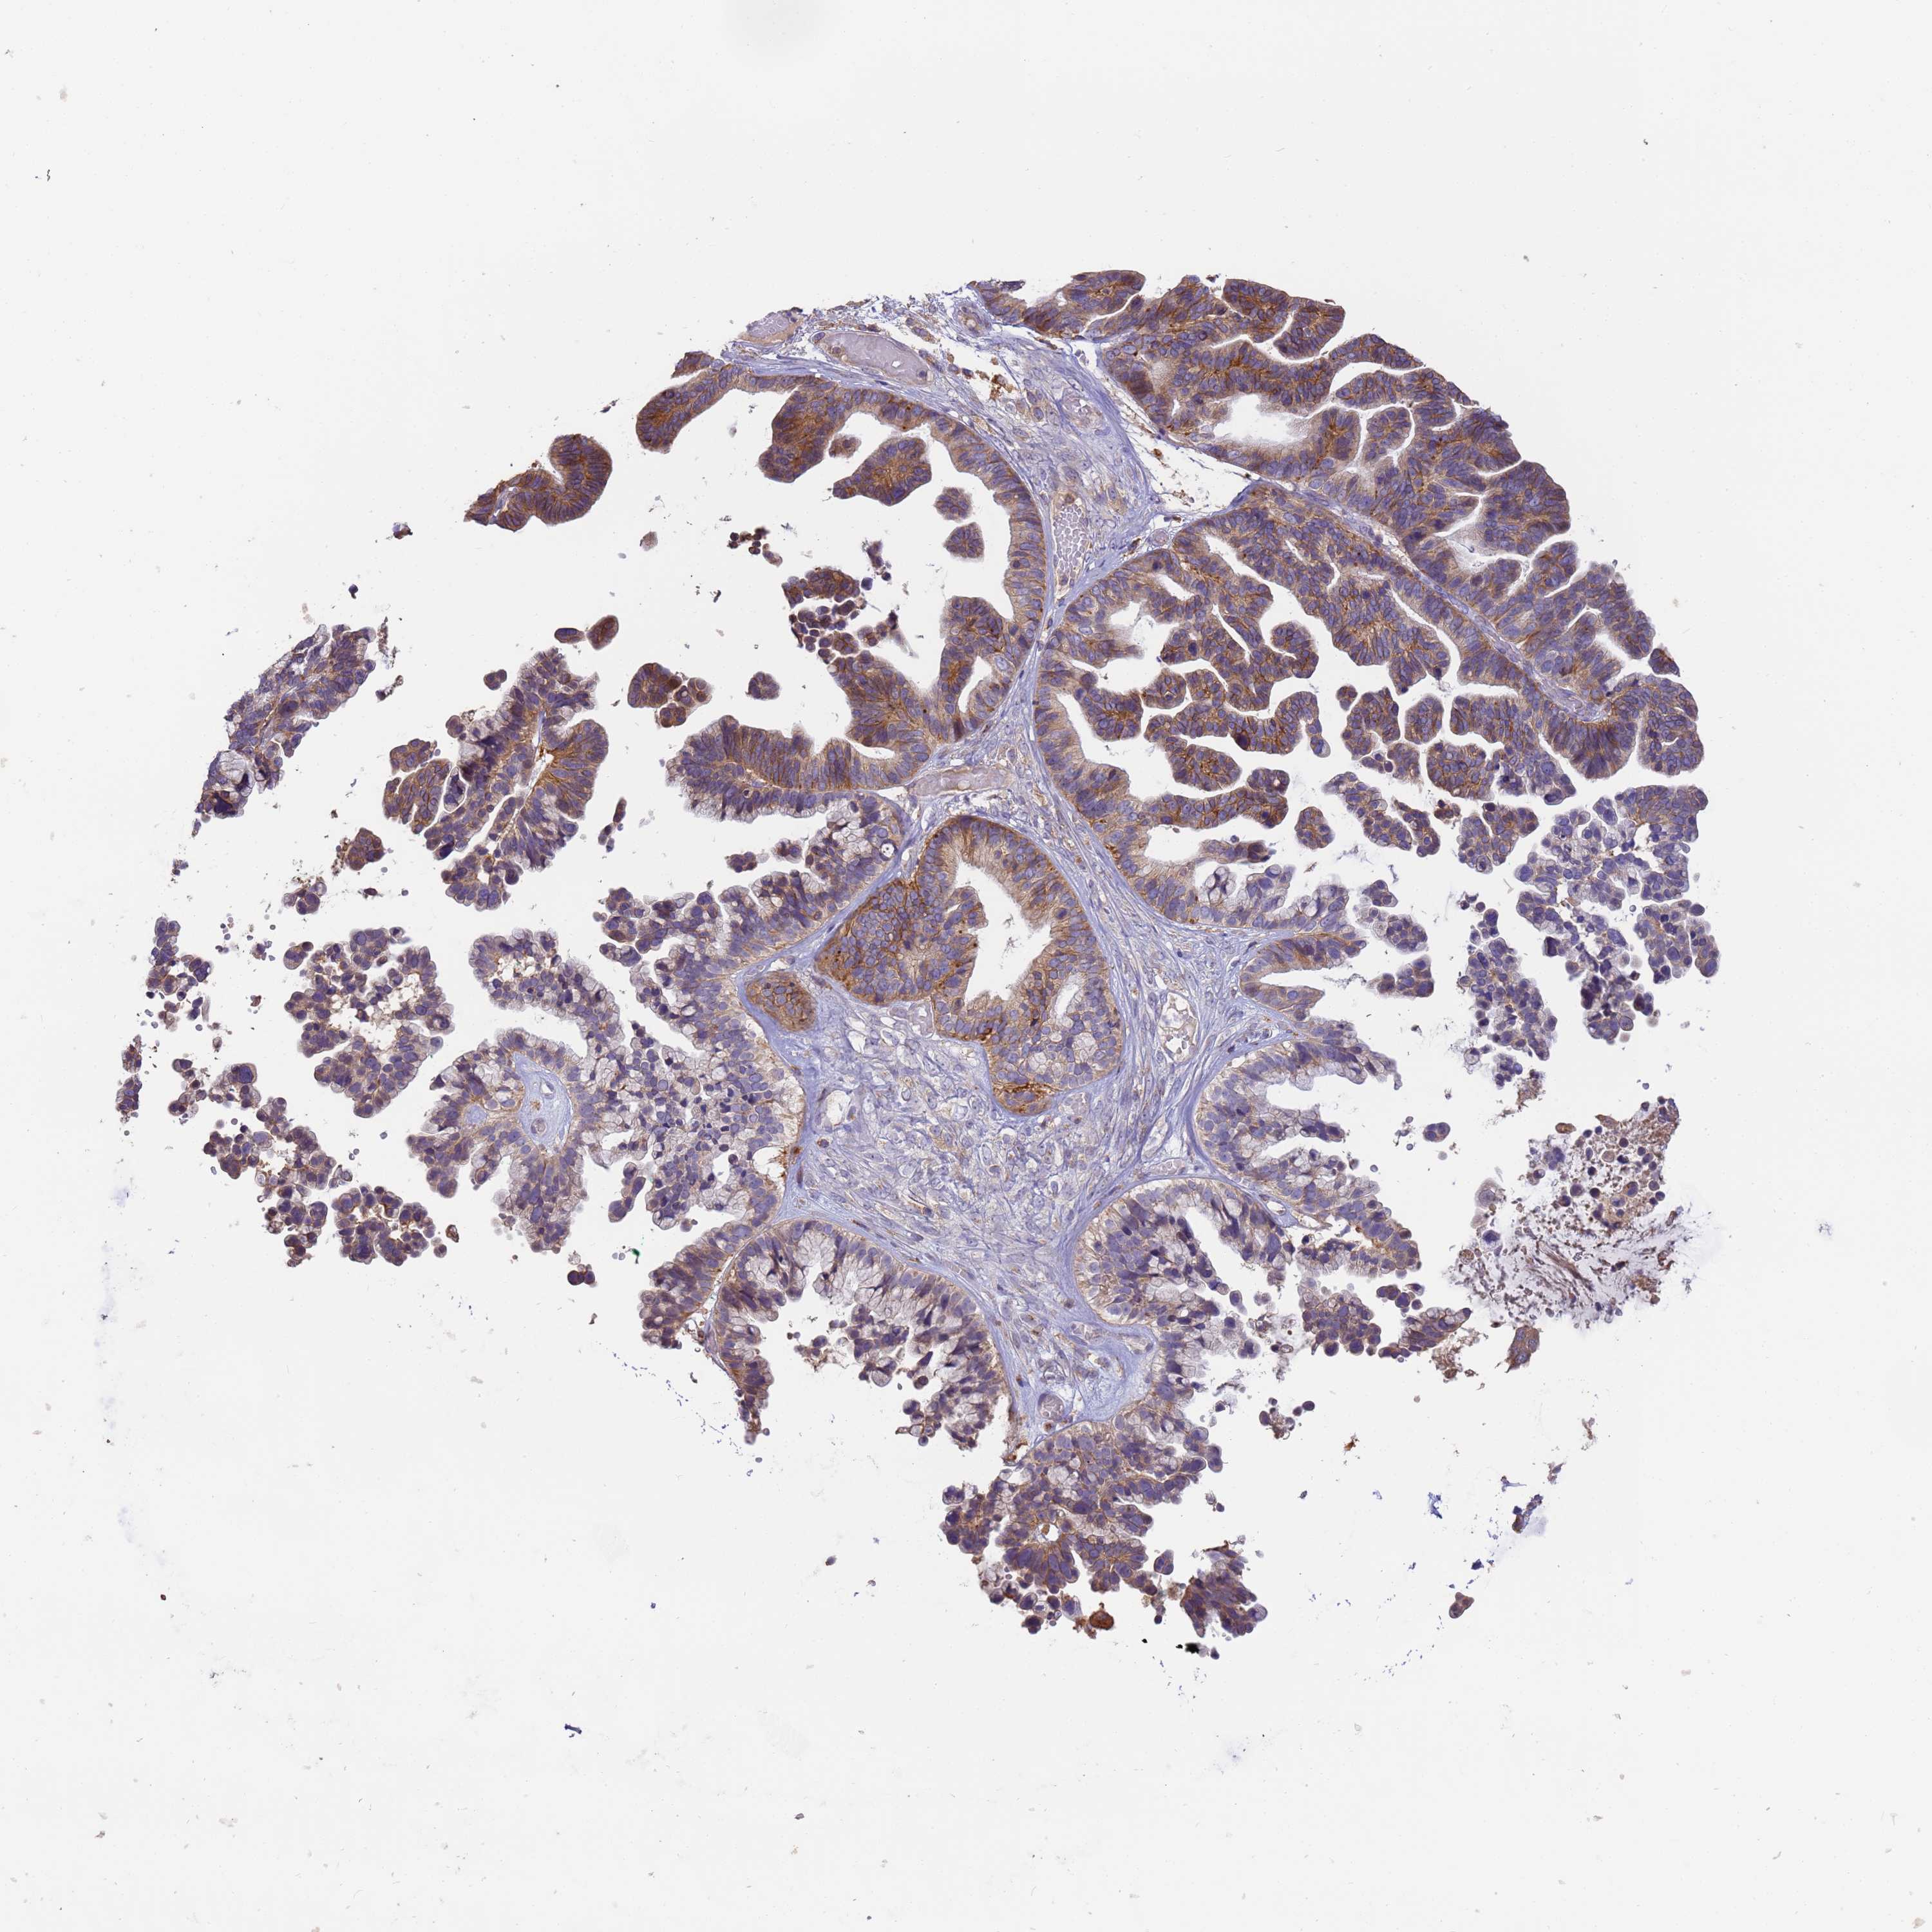

OVARIAN CANCER - Protein expressioni

A mouse-over function shows sample information and annotation data. Click on an image to view it in a full screen mode. Samples can be filtered based on level of antibody staining by selecting one or several of the following categories: high, medium, low and not detected. The assay and annotation is described here.

Note that samples used for immunohistochemistry by the Human Protein Atlas do not correspond to samples in the TCGA dataset.

Antibody stainingi

Antibody staining in the annotated cell types in the current human tissue is reported as not detected, low, medium, or high, based on conventional immunohistochemistry profiling in selected tissues. This score is based on the combination of the staining intensity and fraction of stained cells.

Each image is clickable and will lead to virtual microscopy that enables deeper exploration of all samples and also displays staining intensity scores, fraction scores and subcellular localization as well as patient and tissue information for each sample.

Antibody HPA040445

Antibody CAB034464

Staining

High

Medium

Low

Not detected

Intensity

Strong

Moderate

Weak

Negative

Quantity

>75%

75%-25%

<25%

None

Location

Nuclear

Cytoplasmic/membranous

Cytoplasmic/membranous,nuclear

Carcinoma, endometroid